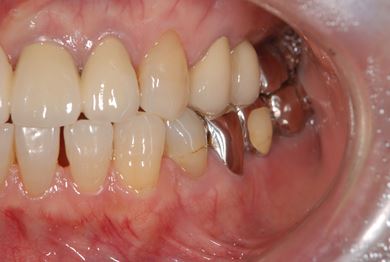

インプラントの症例写真 IMPLANT

骨再生スピードインプラント治療+セラミック治療

| 治療方針 | 骨再生法によりインプラント治療を可能にする。抜歯と同時にインプラント埋入を行い、治療期間を短縮する。 | ||||||||||||||||||||||||||||||||

| 治療内容 | インプラント3本(抜歯即日スピードインプラント、GBR)、メタルボンドセラミッククラウン4本 | ||||||||||||||||||||||||||||||||